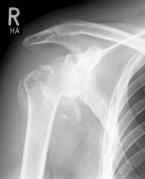

Abbildung2Abbildung1

left: X-ray image of an omarthrosis

right: X-ray of a healthy shoulder joint

X-rays can be used to reliably diagnose the extent of joint wear. In the case of severe osteoarthritis, for example, the joint space and the formation of jagged edges (osteophytes) can be detected. If additional damage to the tendons of the shoulder (rotator cuff) is suspected, ultrasound examination (sonography) or magnetic resonance imaging (MRI) can help clarify the situation.